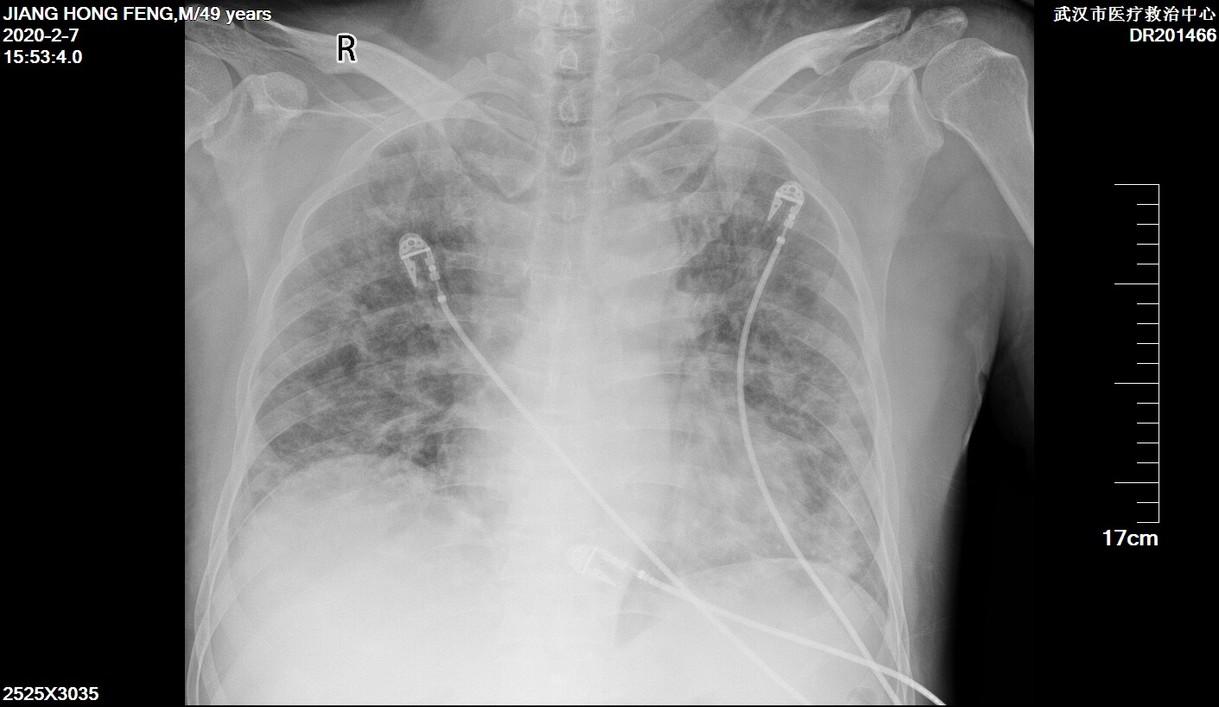

在ICU排的胸片,满肺都是絮状的阴影。